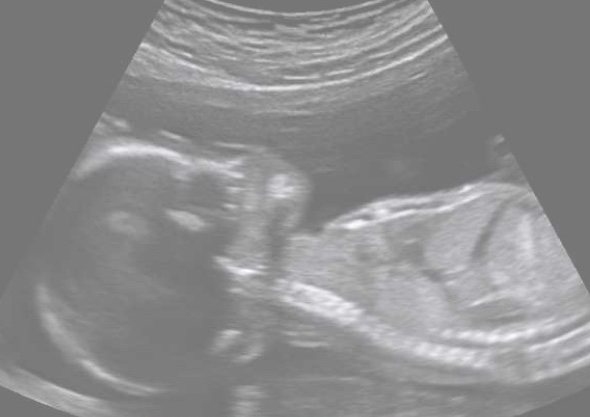

‘You must turn, head down, facing the great mothers back, chin to chest and hands on heart! I will follow you.’

The wonderland pulled up over Nick’s head, shoulders and hips until he could sense a light at the end of a long tunnel.

A mighty surge pushed him downwards and his head came free.

There was glorious brightness all around him.

His body spun and his shoulders, hips and feet came sliding out into a giant cool watery wonderland.

The great mothers gentle hands grasped him strongly and brought him up to her bosom where she looked upon him and cried tears of joy.